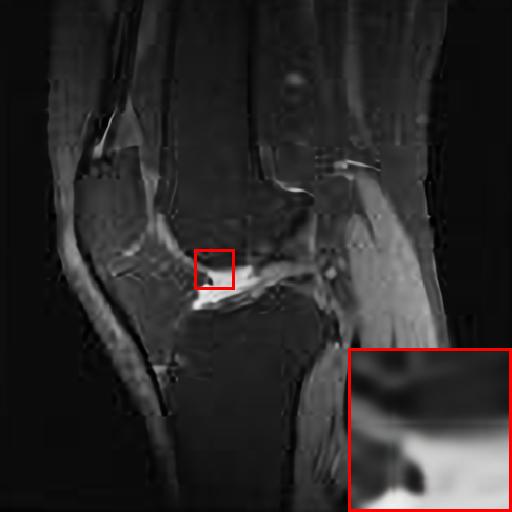

Figure 3: Reconstruction results of each algorithm for MRI images of the knee.

The PNSR/SSIM test results for the knee MRI test images for all contrast methods are shown in Table 1. The PNSR/SSIM test results for the abdominal MRI images are shown in Table 2. It’s worth noting that all metrics were calculated on cropped photos in order to eliminate the impact of non-subject areas. The quantitative results show that for knee MRI images, our proposed TT\mathrm{T}-GAN model achieves the best performance on the PSNR/SSIM metrics. For abdominal MRI images, our model essentially achieves optimal performance, with individual image WDSR slightly outperforming our model. The experimental results cousin that our model is more suitable for medical image super-resolution reconstruction than the existing deep learning-based image super-segmentation models.

We likewise give the visualization comparison results for each comparison algorithm, as shown in Fig. 3 and Fig. 4. It can be seen that the reconstructed images based on bicubic interpolation and deep learning based EDSR and WDSR both show oversmoothing phenomenon and some loss of detail information of the images. In contrast, our T-GAN performs better for the reconstruction of detail information due to the texture Transformer structure.